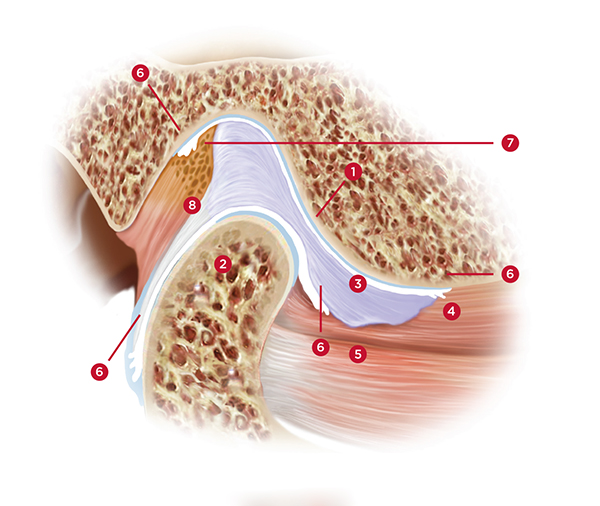

Also, constant tension within the superior belly of the lateral pterygoid muscle (the portion of the lateral pterygoid with attachments to the articular disc) will result in continuous stretching of the ligaments that attach the disc to the posterior surface of the condyle. This constant stretching can eventually create an unstable condyle-disc assembly, resulting in a disc that can click or pop off of and onto the lateral pole of the condyle during function (Figure 1).18 Further damage can be created if the medial aspect of the disc slides forward and off of the condylar head. This severe situation can result in the head of the condyle pressing against the highly innervated and vascular retrodiscal tissue. This can be experienced as extreme pain in the joint whenever the patient attempts to close their mandible or bite into food. If left untreated, this could eventually lead to bone-on-bone contact between the head of the condyle and the eminence and potential degeneration of the condylar head.19

(1.) Lateral view of cross-section through the TMJ: [1] Posterior slope of the eminentia; [2] condyle; [3] disc; [4] superior lateral pterygoid muscle; [5] inferior lateral pterygoid muscle; [6] synovial tissue; [7] retrodiscal

tissue; [8] posterior ligamentous attachment of disc to condyle.

Figure 1